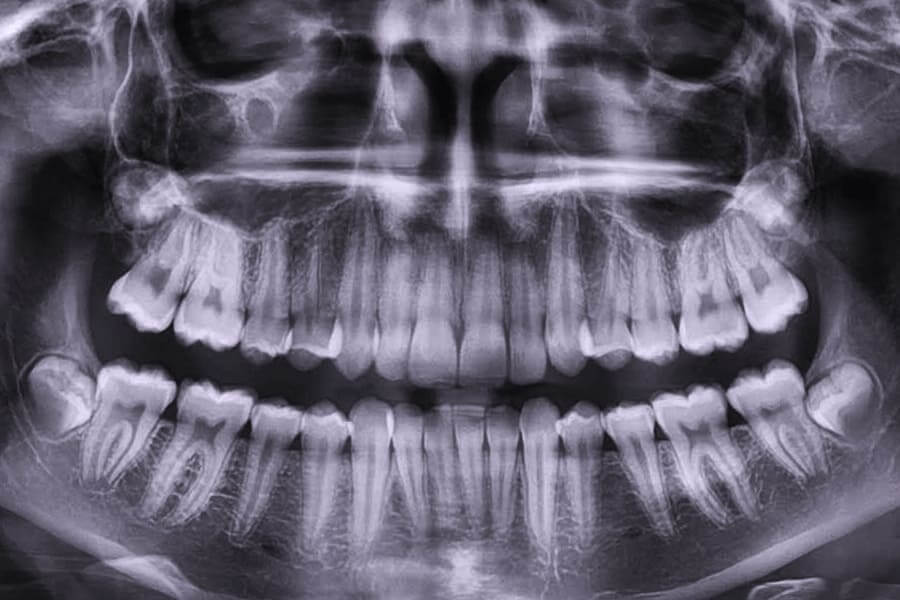

Эффективное и безопасное лечение конечно же без компьютерной 3D-томографии невозможно. Без неё, на обычных (проекционных) рентгеновских снимках можно многое не увидеть и пропустить!

Проекционные снимки позволяют увидеть лишь общую рентгенологическую тень, тогда как толщина исследуемой зоны может достигать до 2,5 см, а плотность тканей существенно различаться!

Именно компьютерная томография позволяет исследовать ткани послойно, в 3-х взаимно перпендикулярных плоскостях сразу, выводя изображение тремя картинками на монитор.